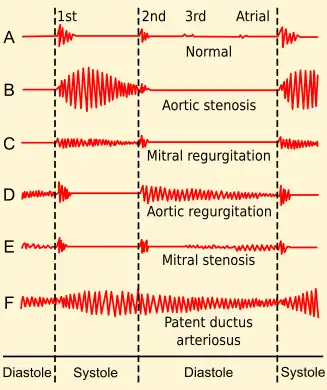

In healthy adults, there are two normal heart sounds, often described as a lub and a dub that occur in sequence with each heartbeat. These are the first heart sound (S1) and second heart sound (S2), produced by the closing of the atrioventricular valves and semilunar valves, respectively. In addition to these normal sounds, a variety of other sounds may be present including heart murmurs, adventitious sounds, and gallop rhythms S3 and S4.

Heart murmurs are generated by turbulent flow of blood and a murmur to be heard as turbulent flow must require pressure difference of at least 30 mm of Hg between the chambers and the pressure dominant chamber will outflow the blood to non-dominant chamber in diseased condition which leads to Left-to-right shunt or Right-to-left shunt based on the pressure dominance. Turbulence may occur inside or outside the heart; if it occurs outside the heart then the turbulence is called bruit or vascular murmur. Murmurs may be physiological (benign) or pathological (abnormal). Abnormal murmurs can be caused by stenosis restricting the opening of a heart valve, resulting in turbulence as blood flows through it. Abnormal murmurs may also occur with valvular insufficiency (regurgitation), which allows backflow of blood when the incompetent valve closes with only partial effectiveness. Different murmurs are audible in different parts of the cardiac cycle, depending on the cause of the murmur.

- Regurgitation through the mitral valve is by far the most commonly heard murmur, producing a pansystolic/holosystolic murmur which is sometimes fairly loud to a practiced ear, even though the volume of regurgitant blood flow may be quite small. Yet, though obvious using echocardiography visualization, probably about 20% of cases of mitral regurgitation do not produce an audible murmur.[3]

- Stenosis of the aortic valve is typically the next most common heart murmur, a systolic ejection murmur. This is more common in older adults or in those individuals having a two-leaflet, not a three-leaflet, aortic valve.

- Regurgitation through the aortic valve, if marked, is sometimes audible to a practiced ear with high quality, especially electronically amplified, stethoscope. Generally, this is a very rarely heard murmur, even though aortic valve regurgitation is not so rare. Aortic regurgitation, though obvious using echocardiography visualization, usually does not produce an audible murmur.

- Stenosis of the mitral valve, if severe, also rarely produces an audible, low frequency soft rumbling murmur, best recognized by a practiced ear using high quality, especially electronically amplified, stethoscope.

- Other audible murmurs are associated with abnormal openings between the left ventricle and right heart or from the aortic or pulmonary arteries back into a lower pressure heart chamber.